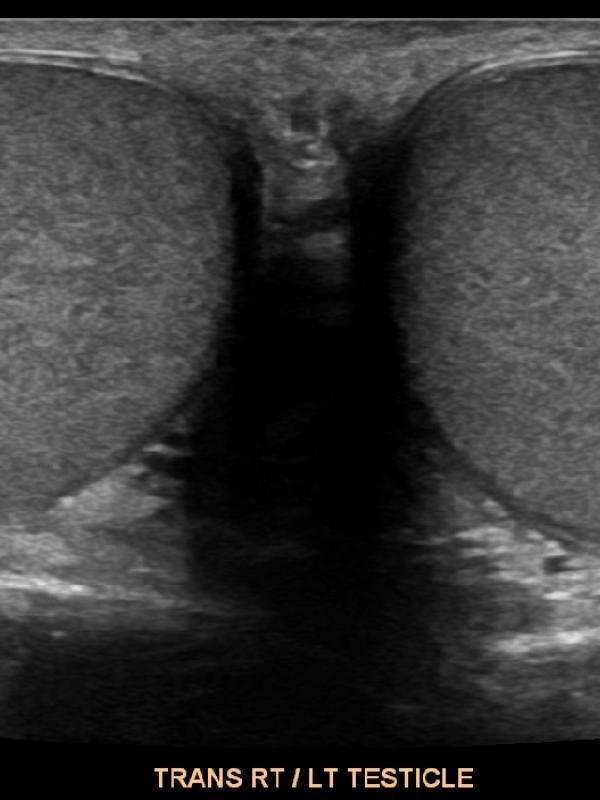

Scrotal ultrasound FAQ

Scrotal ultrasound

Ultrasound imaging is the primary diagnostic modality used to evaluate the scrotum/testicles. Referring providers will order a scrotal ultrasound for a number of reasons. The most common reasons are: testicular pain, a lump is discovered, or if a hernia is suspected. Undescended testis.

• Will the ultrasound of the scrotum and testicles be painful? No. The ultrasound exam will not be painful at all. The sonographer uses warm ultrasound gel and very light pressure from the transducer to image the testicles and scrotal contents.

• Is there any preparation required for a scrotal ultrasound exam? No, there is no preparation needed before having a scrotal ultrasound.